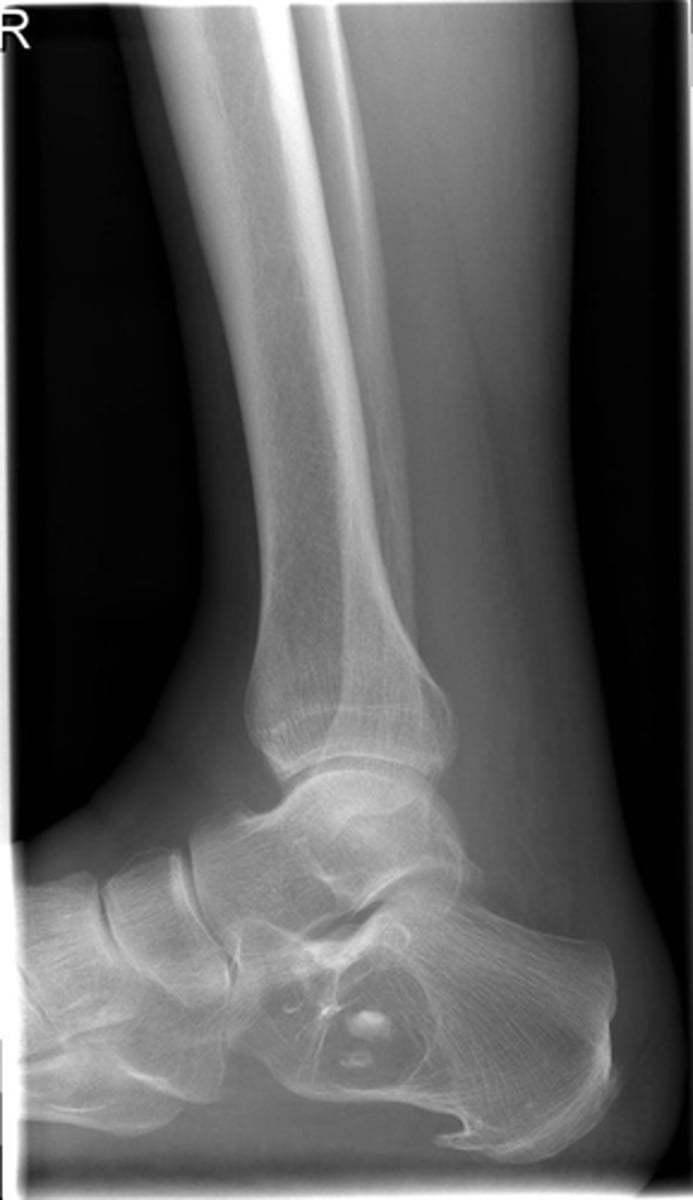

- Body of calcaneus

- Geographic

- Lucent

- Central target sequestrum

Describe the lesion

<p>Describe the lesion</p>

Intraosseous lipoma

Most likely diagnosis?

<p>Most likely diagnosis?</p>

Refer to orthopedist or specialist

Next step?

<p>Next step?</p>

Heel spur

What is going on with the posteroinferior calcaneus?

<p>What is going on with the posteroinferior calcaneus?</p>